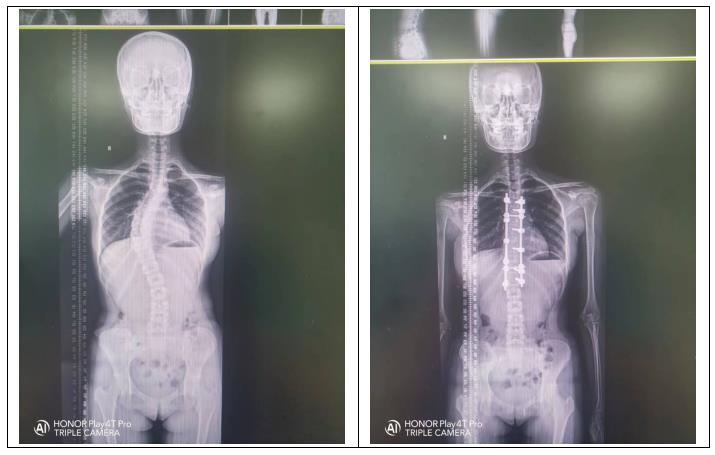

一、什么是脊柱侧弯? 脊柱侧弯:又称脊柱侧凸,它是一种脊柱的三维畸形,包括矢状位、冠状位和轴位的序列异常。如果正位全脊柱X线片显示cobb角大于10°的侧方弯曲,即可诊断。

三、脊柱侧弯治疗原则1、 早发现、早诊断、早干预、早治疗一越早越好;2、 不同类型、不同年龄阶段的治疗原则完全不同;3、 一旦发现,必须咨询专业的脊柱外科医师;4、 根据Cobb角大小选择不同治疗方法: 当Cobb角大于40°,可选择手术治疗 当Cobb角小于40°大于20°,可矫形器治疗配合物理治疗、矫正体操。 当Cobb角小于20°,可物理治疗及矫正体操。 当Cobb角小于10°,观察,并定期复查。 标准化的阶梯治疗流程

4、手术治疗 青少年特发性脊柱侧弯的手术指征:侧弯角度 >40° ,支具治疗无效,侧弯进展速度>5°/年和外观畸形明显者。手术治疗是通过钛合金或不锈钢螺钉和棒等内固定技术将弯曲的脊柱慢慢拉直固定,然后将移植骨覆盖于脊柱后方使弯曲的脊柱长在一 起,从而达到预防脊柱弯曲加重,改善心肺及消化功能的目的。